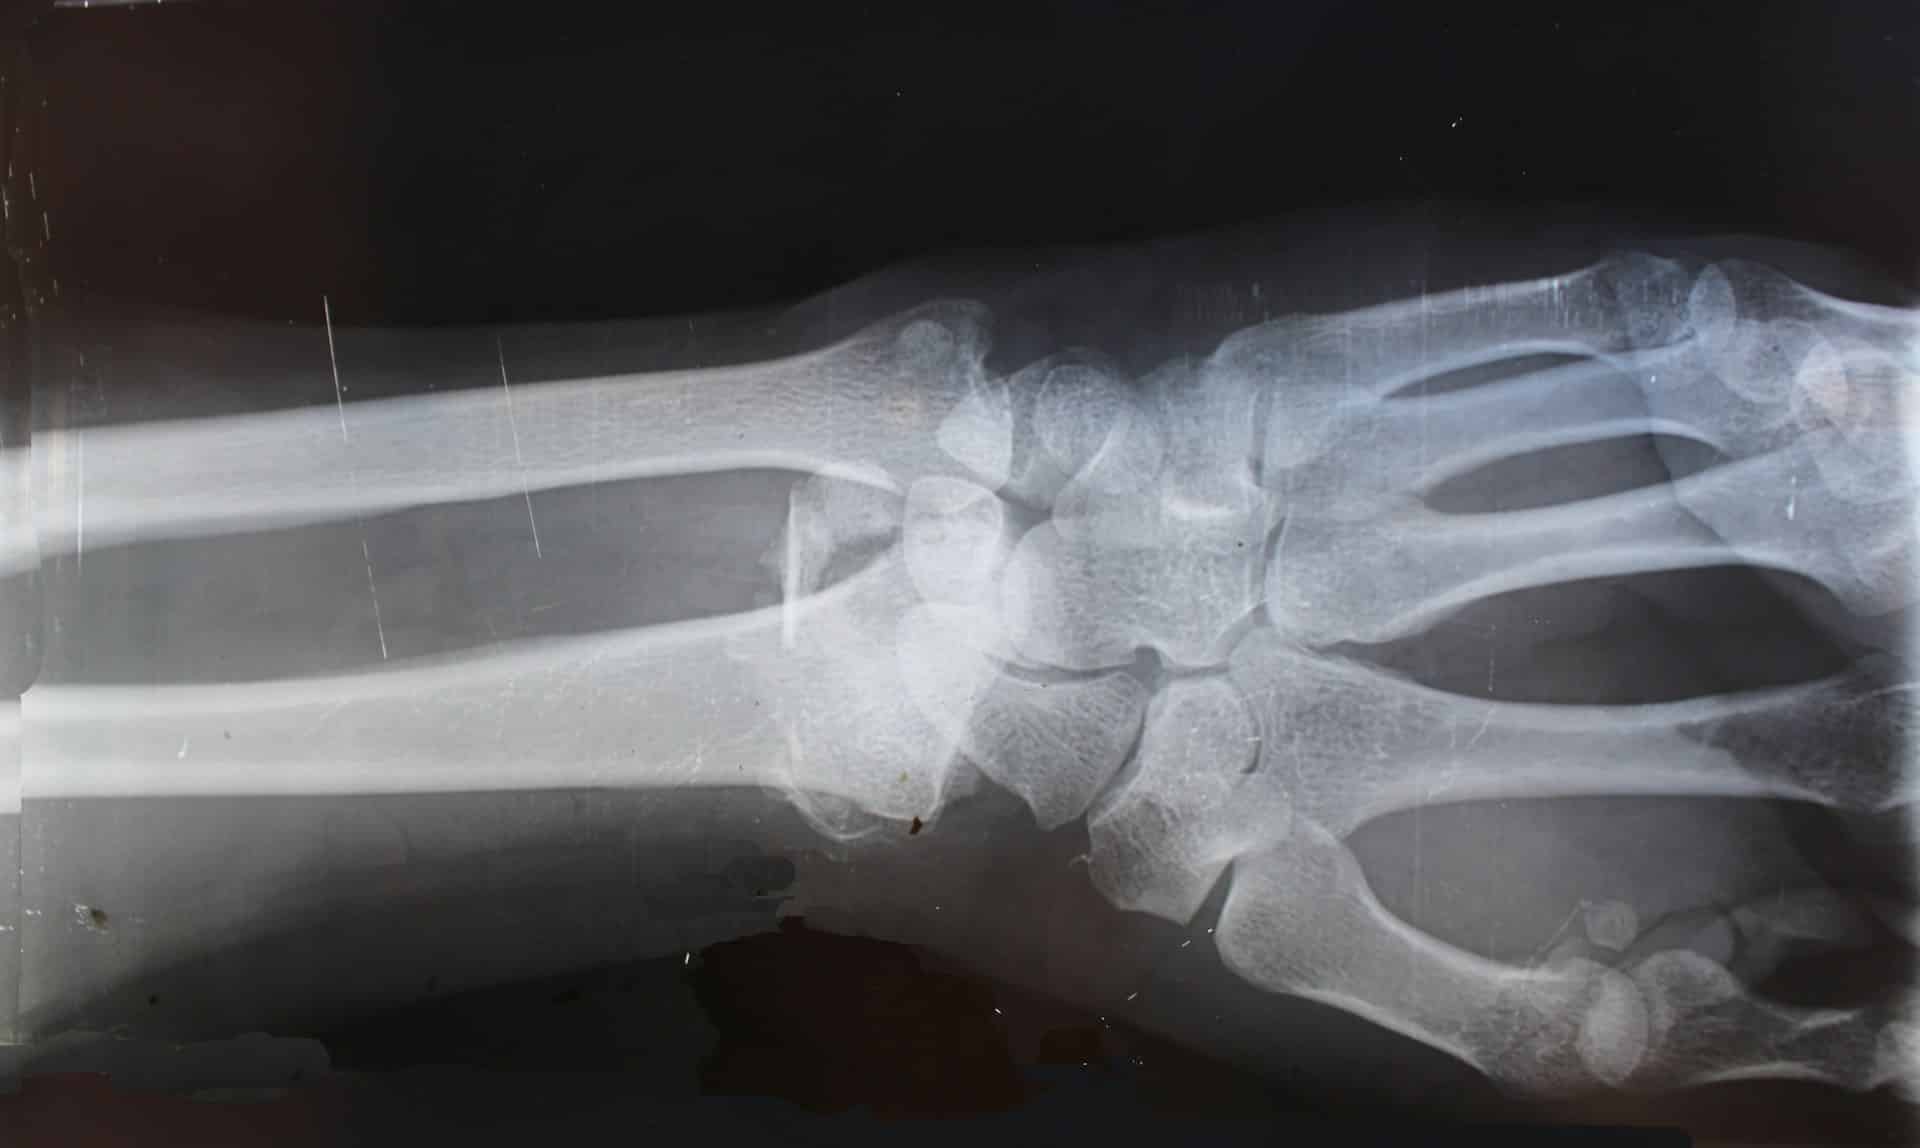

Fractures or broken bones are generally common for everyone, from kids to adults. In fact, it is estimated that one person will likely have at least two broken bones throughout their lifetime. These injuries happen because the force on the bone is stronger than what the bone can handle, resulting in what medical professionals call a fracture.1 A statistic revealed in 2010 that broken bones were the second leading cause of injury among Canadians, with a greater likelihood of these injuries impacting adolescents and seniors.

There are several steps related to bone fracture healing that indicate positive progress is being made to ensure the victim can return to their normal life. However, there are extenuating circumstances, such as failed or delayed healing, which can impact up to 10% of fractures. This may be the result of infection or poor blood flow.2

Broken bones are painful. A condition associated with fractures caused by severe accidents is known as chronic fracture pain (CFP). This can negatively impact the healing process and require advanced medical rehabilitation to overcome.3